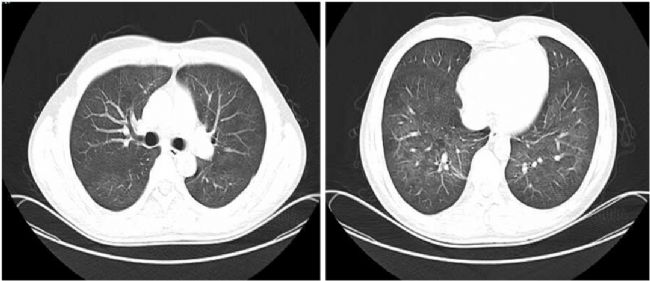

· 胸部CT顯示左上肺有一個(gè)厚壁空洞,可見血管集束征和局部胸膜增厚(如圖1所示)

圖1:治療前胸部CT顯示左上肺厚壁空洞,內(nèi)緣光滑,外緣不規(guī)則,鄰近胸膜和左下胸膜增厚

接受靜脈注射頭孢曲松(2g,每日一次)治療2周,口服磺胺甲惡唑-甲氧芐啶(0.96g,每日兩次)。治療一周后胸痛緩解。治療6周后,胸部CT掃描顯示肺空洞消失,只留下少量斑片狀浸潤。胸膜增厚情況有所改善(圖2)。

圖2:治療6周后胸部CT顯示空洞消失,僅留下少量斑片狀浸潤,胸膜增厚改善